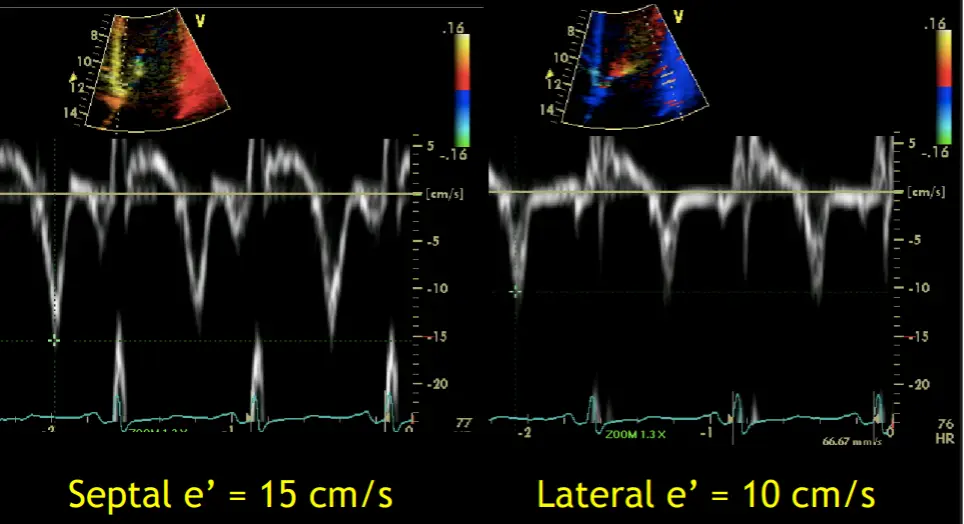

- Preserved e’ velocity (septal ≥ lateral)

- By contrast, with restrictive physiology you will expect reduced e’ velocities

- “Your e’ essentially is the tissue velocity of the mitral annulus. And you can look at the medial e’ and the lateral e’. And by definition, restrictive heart disease, there’s a stiffening of the muscle and it doesn’t relax as well. And so the movement of the muscle is low. And so you’ll have a patient with heart failure, preserved ejection fraction, predominant right-sided symptoms, and your e’ will be low, as you suspect, because there’s diastolic dysfunction. However, with constriction, it’s not a muscle disease. And so you may have normal or elevated e’ velocities in the same clinical context or preserved EF. right-sided symptoms with elevated filling pressures. And so normal or elevated e’ tissue Doppler velocities of the mitral annulus can help promote that it’s constriction and not restriction. And alternatively, with the E-prime velocities, you can compare the medial e’ velocity to the lateral e’ velocity. And the normal healthy heart, the septum is a little bit restricted because it’s tethered to the cardiac skeleton. And so normally the lateral e’ has a greater velocity. The lateral mitral annulus moves faster than the medial mitral annulus. But in constriction, because of the tethering of the lateral wall to the constricted, inflamed, fibrous pericardium, you’ll have annulus reversus whereby the medial e’ velocity will be greater than the lateral e’ velocity.”

Tissue Doppler

- Rationale: Because the mechanoelastic properties of the myocardium are preserved in patients with constrictive pericarditis, longitudinal early diastolic myocardial velocities are higher than in patients with Restrictive Cardiomyopathy.

- “A mean annular velocity (averaged from 4 walls) 5 cm/s correctly distinguished CP from RCMP, even when there was a large overlap of BNP between the 2 groups.” (Sengupta AJC, 2008)